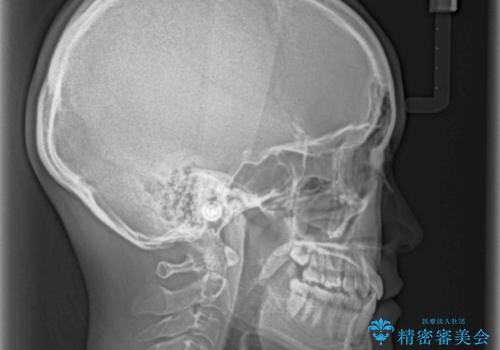

奥歯の反対咬合 上顎骨を拡大してインビザラインで矯正

- 奥歯の反対咬合を気にして来院された患者様です。

反対咬合は上顎骨の幅が下顎骨よりも小さいことが原因なので、拡大装置により骨幅を広げて上下関係を改善し、その後インビザラインにて歯並びを整えることとしました。

反対咬合が改善され、食いしばり癖もなくなり、顎関節の負担が軽減されました。

上顎骨を拡大したことで前歯に隙間ができ、1ヶ月ほど恥ずかしい時期がありましたが、しっかりとした咬み合わせに仕上がり、患者様には大変満足していただきました。